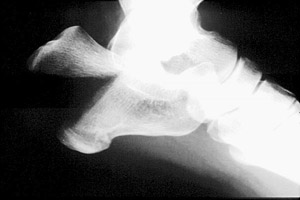

A | Harris radiograph. There is a comminuted fracture of the calcaneus. |